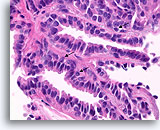

Papillair carcinoom, Borst FNA, Celblok.

Sterkere vergroting van de patiënt uit afbeelding 39-43 toont een fibrovasculaire kern (open pijl) en een cribriform gebied dat consistent is met een papillair carcinoom (pijl).

10X

Papillair carcinoom, Borst FNA, Celblok.

Sterkere vergroting van de patiënt uit afbeelding 39-43 toont een fibrovasculaire kern (open pijl) en een cribriform gebied dat consistent is met een papillair carcinoom (pijl).

10X

Papillair carcinoom, Borst FNA, Celblok.

Een ander cribriform gebied (pijl) en een fibrovasculaire kern (open pijl) kunnen gemakkelijk worden onderscheiden.

10X

Papillair carcinoom, Borst FNA, Celblok.

Een ander cribriform gebied (pijl) en een fibrovasculaire kern (open pijl) kunnen gemakkelijk worden onderscheiden.

10X

Papillair carcinoom, Borst FNA, Celblok.

Een sterkere vergroting van het diagnostische cribriforme patroon in afbeelding 45 toont een monotone celpopulatie met gerandomiseerde polariteit die gladde, ronde ruimten vormt. Necrotisch materiaal is focaal aanwezig in één lumen.

40X

Papillair carcinoom, Borst FNA, Celblok.

Een sterkere vergroting van het diagnostische cribriforme patroon in afbeelding 45 toont een monotone celpopulatie met gerandomiseerde polariteit die gladde, ronde ruimten vormt. Necrotisch materiaal is focaal aanwezig in één lumen.

40X